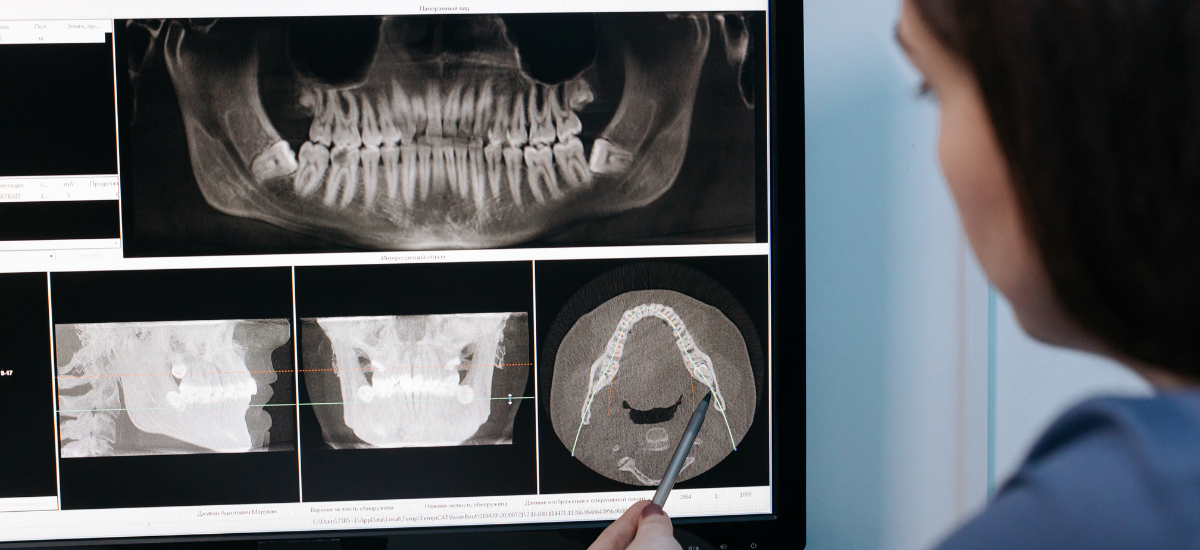

歯科医院では、レントゲンやCTを使って骨の状態を正確に確認できます。

「もう手遅れかも…」と思っても、まずは歯科でレントゲンやCTによる精密検査を受けてみてください。

骨の吸収量や炎症の範囲を正確に把握することで、最適な治療方法が見つかります。

そのため、治療を検討する際は、歯科用CTやレントゲンによる精密検査で骨の形や厚みをしっかり確認することが大切です。

重度歯周病の進行度は、外から見ただけでは分かりにくく、レントゲンやCT撮影で顎の骨の吸収状態を確認することで、初めて正確に把握できます。

歯を支える骨がどのくらい残っているのか、炎症がどの範囲に広がっているのかを診断し、それに合わせた治療計画を立てることが重要です。